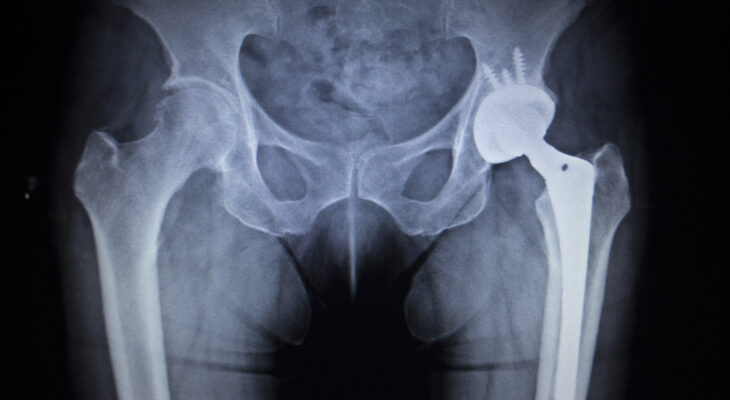

Plaučių embolijos priežastys ir rizikos veiksniai

Plaučių embolija – tai rimta būklė, kai į plaučių arteriją ar jos šakas patenka ir ją užkemša svetimkūnis. Dažniausiai tai ...